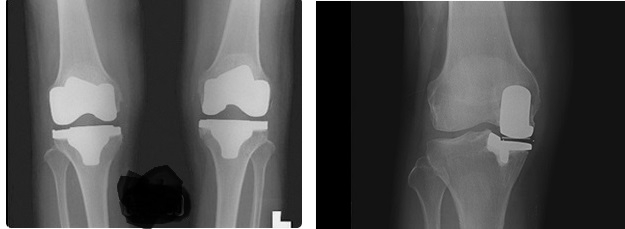

퇴행성관절염은 관절이 노화되면서 생긴다. 체중의 75~90%가 부하되는 무릎이 가장 취약하다. 약물과 주사요법만으로 치료가 힘들 만큼 상태가 악화되면 결국 관절 자체를 교체해줘야 한다. 무릎 인공관절 수술은 손상된 관절 연골 부분을 절제한 뒤 특수 금속으로 제작한 인공관절을 넣어 통증을 없애고, 운동성을 회복시켜주는 수술이다. 수술 방식은 크게 전치환술과 부분치환술로 구분한다.

전치환술은 한마디로 퇴행성 관절염 환자에게 적용하는 마지막 방법이라고 할 수 있다. 대퇴원위부, 경골근위부의 연골판, 십자인대, 관절연골과 뼈 부분 등 무릎 전체를 제거한 뒤 환자 무릎 구조와 가장 흡사한 규격의 인공관절을 만들어 새로 끼워 넣는 방법이다.

이와 달리 부분치환술은 최대한 환자의 인대와 구조물을 살리면서 관절염이 심한 곳의 조직만을 제거한 뒤 여기에 맞춰 인공관절 조직을 삽입하는 방법이다. 이 경우 환자는 전치환술에 비해 조직의 이물감을 덜 느끼며, 수술 다음날부터 목발 없이 걸을 수 있을 정도로 운동성도 좋은 편이다. 또 관절염이 발생한 부위만 선택적으로 수술하기 때문에 골 손실이 적어 향후 부작용이 생길 가능성이 적고, 문제가 생겨도 이후 다양한 치료가 가능하다.

전치환술은 10~12cm 가량을 절개, 무릎 조직 전체를 드러낸 상태에서 수술을 하지만, 부분치환술은 7~8cm만 절개하기 때문에 출혈이 적고, 회복 기간도 짧다. 특히 부분치환술의 경우 출혈량이 100cc 내외로 전치환술의 4분의 1 정도에 불과하기 때문에 수혈량을 최소로 줄이는 것이 가능하다. 인공관절 수술 후 감염의 가장 큰 원인 중의 하나인 수혈을 대폭적으로 줄여 그만큼 감염 부작용을 줄일 수 있다.